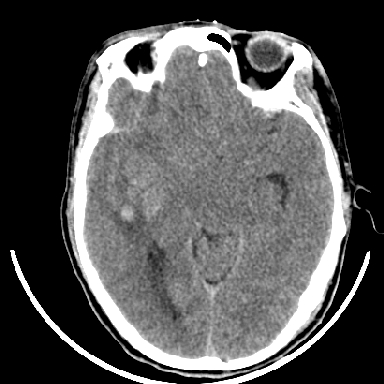

标题: CT6056:脑出血(血管畸形?) [打印本页]

标题: CT6056:脑出血(血管畸形?)

m 40突发头痛左侧偏瘫3小时

支持右侧基底节脑出血

右侧基底节区脑出血.

支持右侧基底节区(主要为外囊区)原发性脑出血。

支持右侧基底节区(主要为外囊区)原发性脑出血----有无血管畸形及动脉瘤或说出血原因待查

术中抽出40ml陈旧血液,血肿底部似见一条索血管影